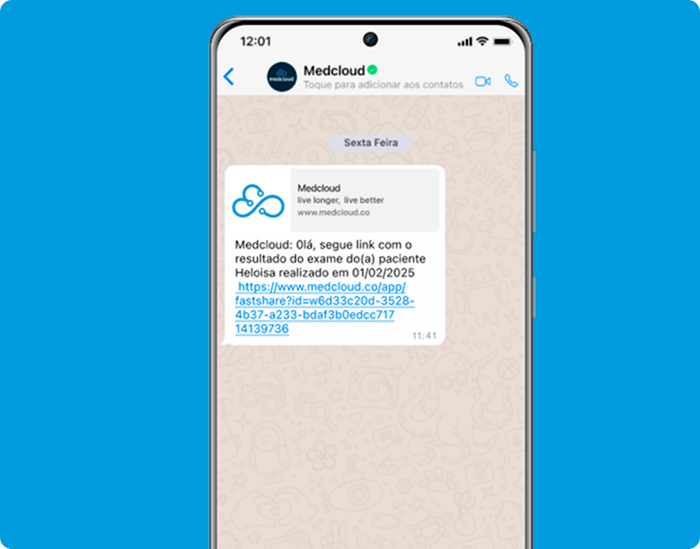

Simple y ágil a través de correo electrónico y WhatsApp para el acceso de sus pacientes y médicos solicitantes.

Acceda a imágenes, informes y archivos adjuntos en su teléfono inteligente. Notificar a los pacientes y solicitantes cuando haya un resultado disponible. Inicie sesión a través del CÓDIGO QR para que los pacientes y

solicitantes puedan acceder a los resultados fácilmente.

Garantice el acceso a los resultados para cualquier perfil de paciente. Comparta los resultados de sus exámenes fácilmente a través de un código QR o un enlace de acceso, incluso sin la aplicación y sin necesidad de iniciar sesión o contraseña.

Acceda a imágenes, informes y archivos adjuntos en su teléfono inteligente. Notificar a los pacientes y solicitantes cuando haya un resultado disponible. Consulte sus resultados desde 1 solo link.